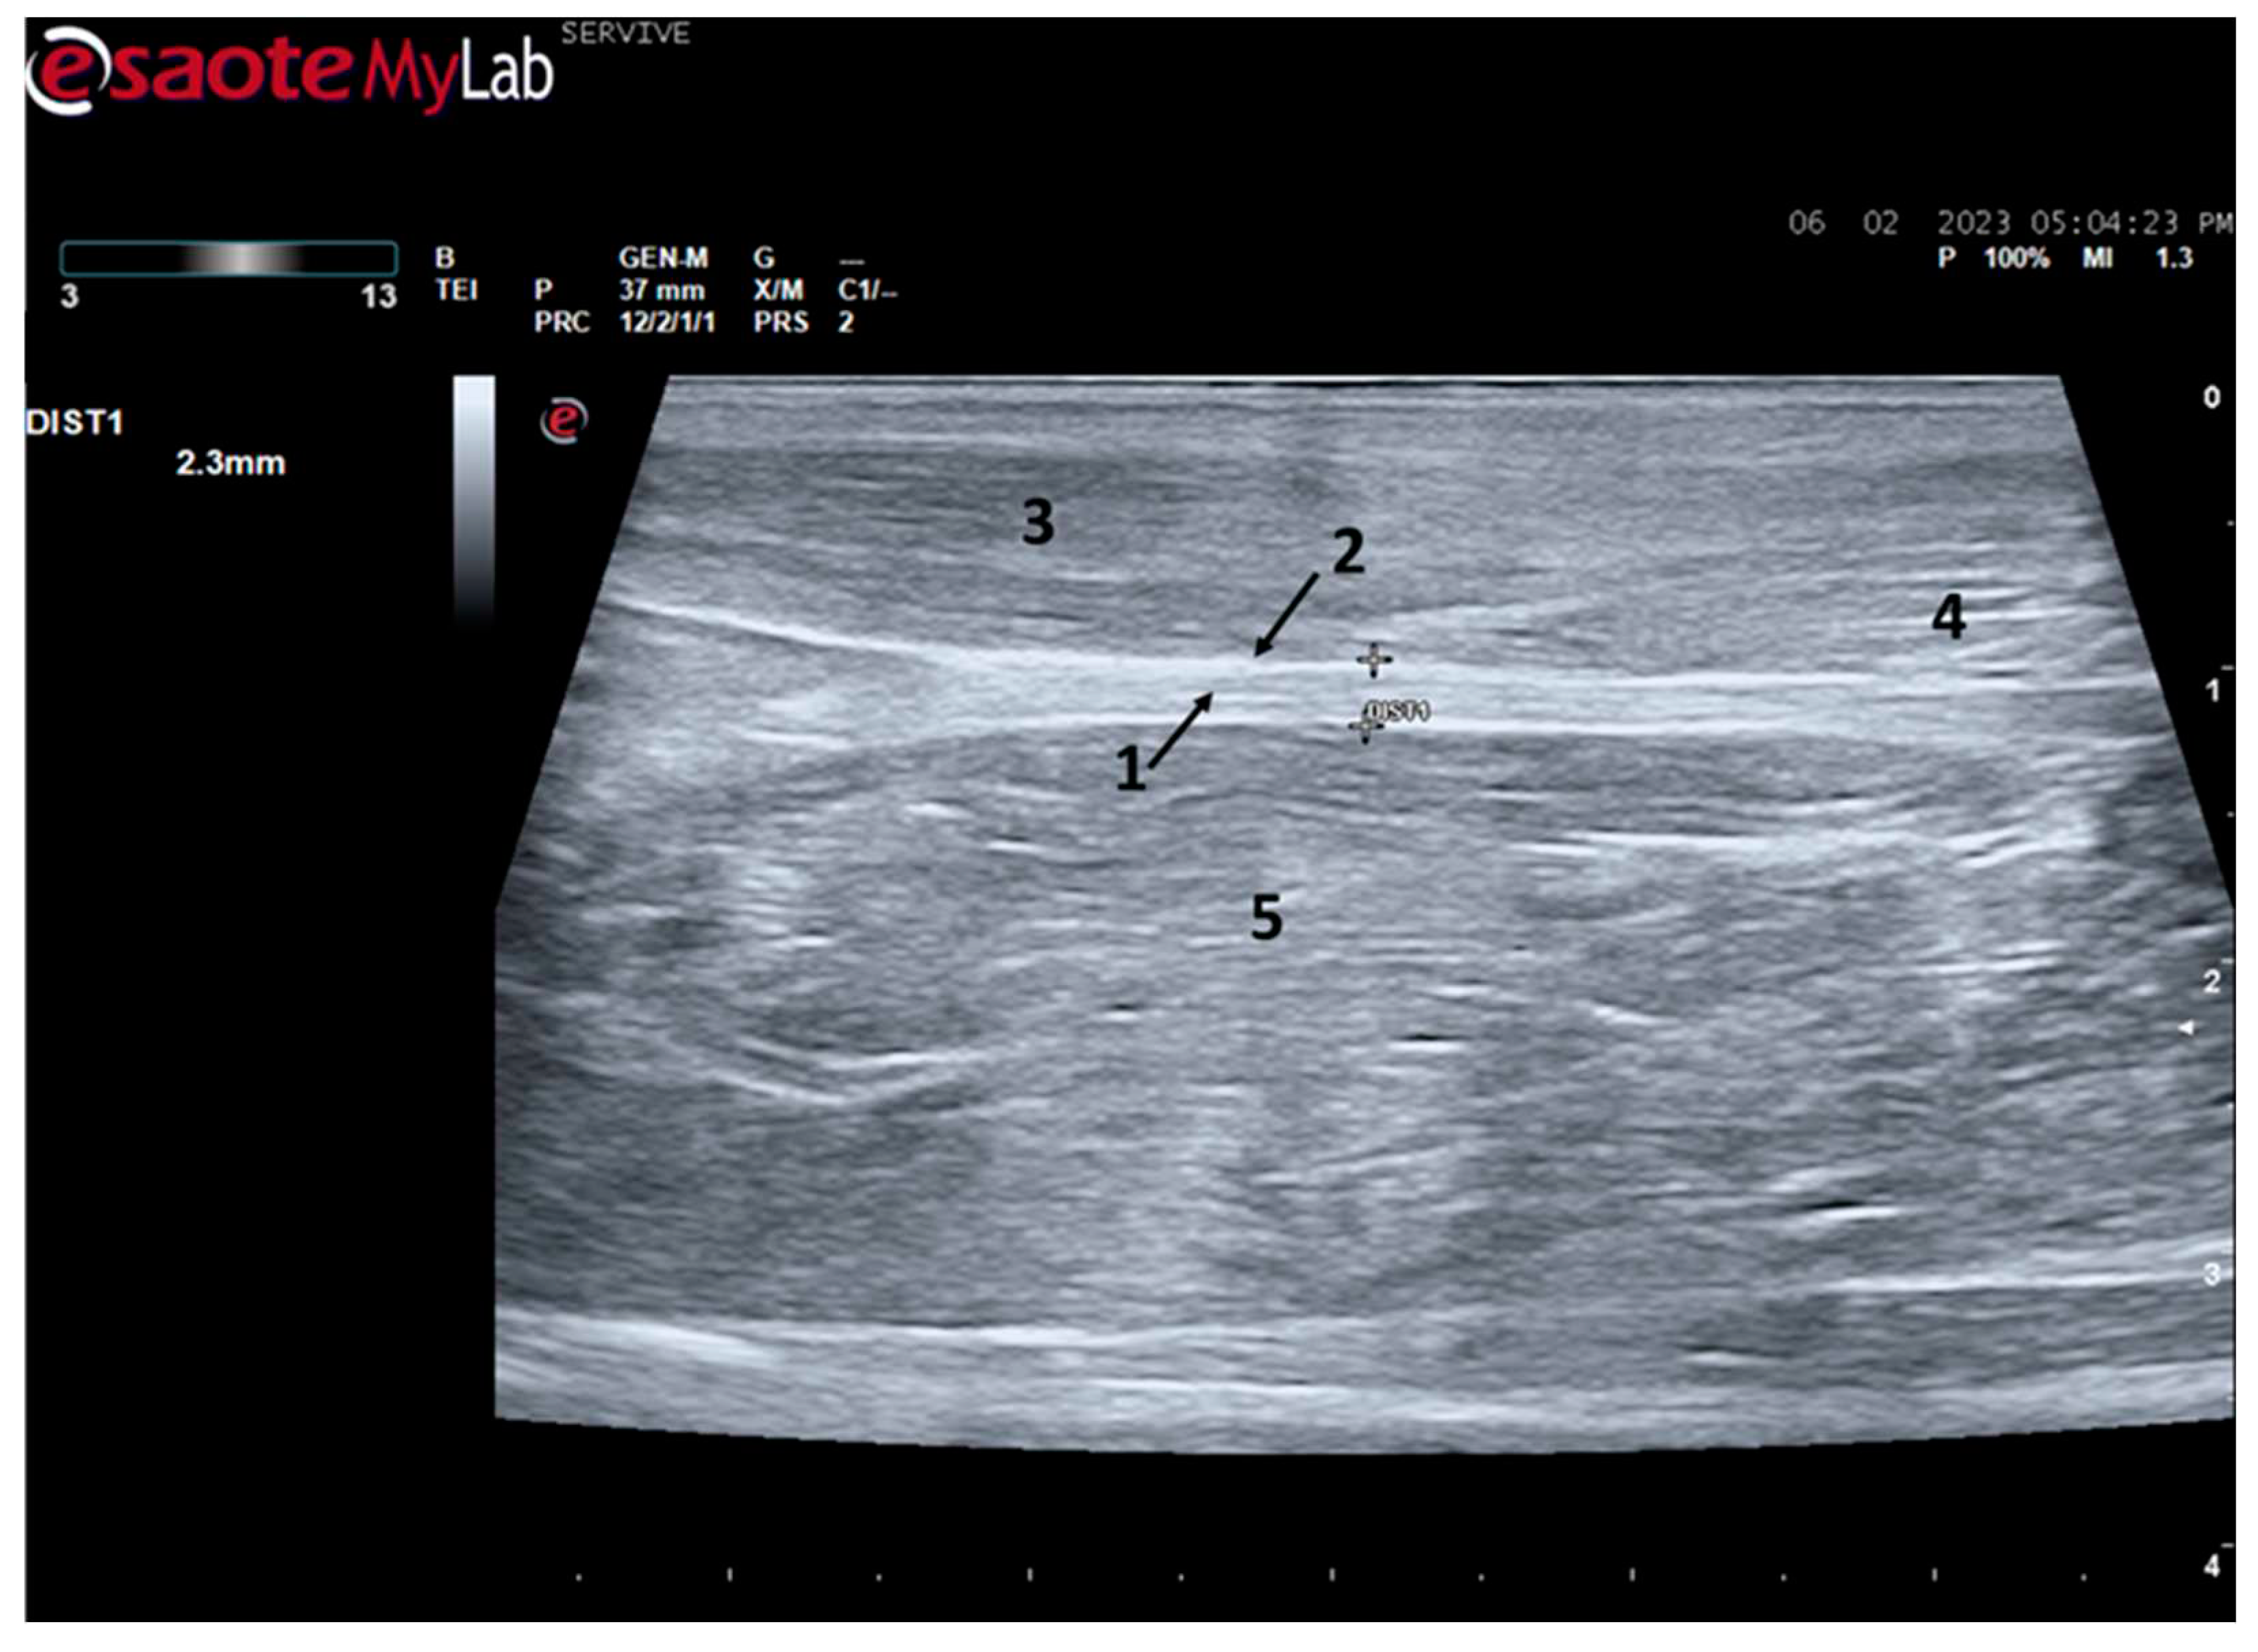

Figure 4.

Ultrasound image of the left sciatic nerve of a sheep nerve halfway through the thigh: 1) sciatic nerve (nerve fascicles enclosed by perineurium); 2) Epineurium; 3) biceps femoris muscle; 4) Piriformis muscle; 5) Adductor muscles. DIST1 represents the measurement of the diameter of the sciatic nerve halfway through the thigh.